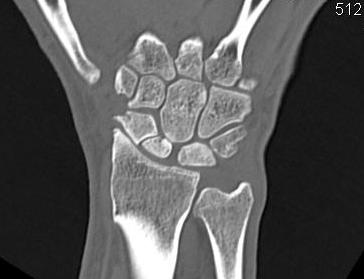

Definition

Scaphoid non union advanced collapse

Diagnosis

Xray / CT

- non union of scaphoid

- radio-scaphoid OA